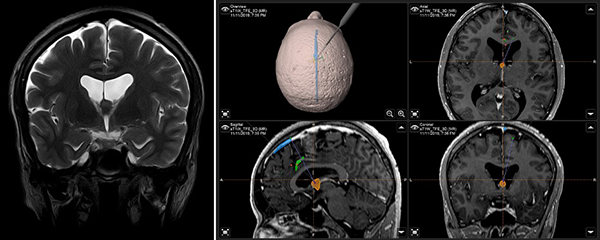

Paciente masculino de 40 años, sin antecedentes patológicos, atendido en nuestra institución por presentar cuadro de 2 años de evolución caracterizado por cefalea holocraneana de moderada intensidad, intermitente. Dos meses previo a la consulta inicial había presentado pérdida de consciencia más un episodio de crisis convulsiva tónico-clónico generalizada. Al examen físico el paciente no presentaba deterioro del sensorio ni déficit neurológico evidente. El resto del examen no mostraba hallazgos relevantes. La resonancia magnética (IRM) evidenció una lesión ovoidea que ocupaba el foramen de Monro, isointensa respecto al parénquima cerebral en las secuencias T1 y T2, de 12x9x9 mm, su margen rostral y dorsal en contacto con el pilar anterior y cuerpo del fornix, respectivamente; con tenue realce a la administración del contraste. En la secuencia de tensor de difusión los diferentes tractos se aprecian con trayecto normal y adecuada disposición de las fibras. Sistema ventricular sin dilatación ni compresiones. Se realizó la exéresis total de la lesión a través de un abordaje interhemisférico transcalloso anterior guiado por sistema de neuronavegación (Figura 1). El curso postoperatorio transcurrió con una hemiparesia braquio-crural derecha transitoria, que cede en días subsecuentes con recuperación total de la fuerza muscular. El paciente fue dado de alta sin déficit neurológico agregado. El examen patológico reportó un quiste coloide. La IRM postoperatoria confirmó la extirpación total de la lesión con cambios postquirúrgicos asociados a craneotomía fronto-parietal derecha (Figura 2). El paciente se encuentra asintomático en seguimiento por la consulta externa.

Figura 1. (A) IRM T2W coronal: ubicación anatómica de la lesión en foramen interventricular; (B) IRM integrada al sistema de neuronavegación, planeación de abordaje quirúrgico.